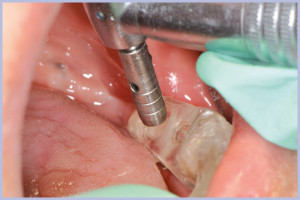

Viene quindi richiesto al tecnico di modificare in laboratorio la mascherina radiologica mediante il posizionamento delle boccole di guida adatte agli impianti da posizionare (Exacone® 6.5 e Exacone® 3,3×8) in asse con gli analoghi del modello Master 3D ed eliminando il repere radiologico standardizzato, trasformandola così nella dima chirurgica (Figg. 14, 15). Si procede quindi alla prova della mascherina sulla paziente per verificarne la stabilità e la corrispondenza esatta con il modello Master 3D (Fig. 16). La seduta chirurgica con tecnica flapless, guida chirurgica e Frese Zero1 dedicate non presenta alcuna difficoltà ; al termine dell’inserimento si posizionano sugli impianti tappi di guarigione bassi per permettere loro di guarire con tecnica sommersa (Figg. 17-27). Si effettua nella stessa seduta una CBCT che dimostra che la posizione clinica degli impianti risulta sovrapponibile a quella progettata dagli Autori (Figg. 28-30).

- Figg. 17, 18 – Passaggio dei mucotomi guidati dalla mascherina chirurgica

- Fig. 18

- Figg. 19, 20 – Passaggio fresa Zero1 attraverso la boccola per impianto Exacone® Ø 3,3

- Fig. 20